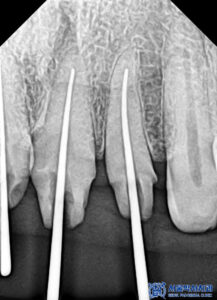

충치를 제거하고

신경치료를 시작하였습니다.

또한 신경치료는 미세한 치아 신경관

하나하나 찾아내어 살리는 진료이기에

정성과 진심을 기울여서 진료하여

자연치아를 오래 사용하실 수 있도록

많은 노력을 들이고 있습니다.

본원에서는

MTA 신경치료를

진행하고 있습니다.